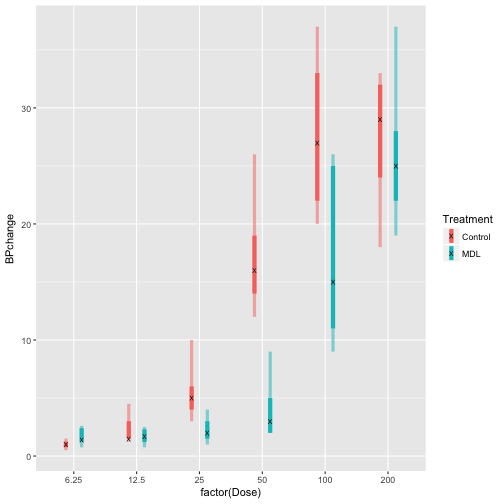

You can even create custom functions to generate stats. The only caveat is that the variable names need to match the agrguments of the geometry being called.

# create min and max range function

range_function <- function(x){

data.frame(ymin = min(x),

ymax = max(x))

}

# demonstrate range function

range_function(Rabbit$BPchange)

## ymin ymax

## 1 0.5 37

# create median interquartile range function (calculates the median, 25% and 75% quartiles)

med_IQR <- function(x){

data.frame( y = median(x),

ymin = quantile(x)[2],

ymax = quantile(x)[4])

}

# demonstarte quantile and med_IQR function

quantile(Rabbit$BPchange)

## 0% 25% 50% 75% 100%

## 0.50 1.65 4.75 20.50 37.00

med_IQR(Rabbit$BPchange)

## y ymin ymax

## 25% 4.75 1.65 20.5

# use functions in stat_summary to plot the data

# redundancy of Treatment variable is necessary to adjust the attributes of the stat_summary functions

p <- ggplot(Rabbit, aes(x = factor(Dose), y = BPchange, color = Treatment, group = Treatment, fill = Treatment))

p +

stat_summary(geom = 'linerange', fun.data = med_IQR, size = 2, position = posn.d) +

stat_summary(geom = 'linerange', fun.data = range_function, size = 1.5, alpha = 0.5, position = posn.d)+

stat_summary(geom = 'point', fun.y = median, shape = "X", color = 'black', size = 2, position = posn.d)